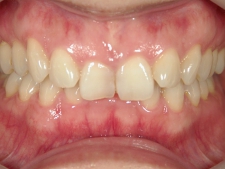

矯正歯科(全顎ワイヤー矯正)治療後

36歳女性 磐田市

在住

治療期間2年6

ヶ月